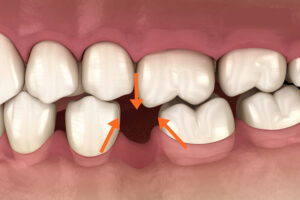

提到牙齒矯正,我想大家最關切的問題一定是,我的矯正需不需要拔牙?大約80%的患者都強烈的希望可以不拔牙就完成矯正治療。的確,矯正拔不拔牙我想也是治療計畫中最最重要的決定,因為牙齒一旦拔了就永遠回不來了…